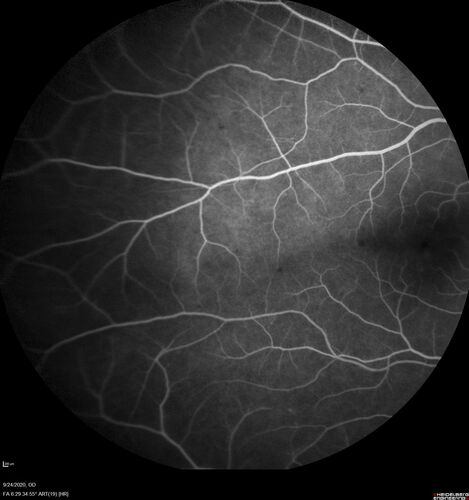

Elevated Episcleral Venous Pressure and Retinal Hemorrhages in both eyes

78 year old female with chronic red eye.   The eyes are red all the time now.  She is on Xeralto because of a history of blood clots in her lungs (2005 about).  She has not had problems since.  She has had floaters for many years.  Ever since her eyes got funny she sees more floaters in both eyes.  She had a brain scan over 6 months ago which was OK.  She also had double vision when this first started which went away.  She could not drive for a few months.

VA OD: Dcc20/32-1

VA OS: Dcc20/125

IOP: TP: OD:17 OS:16

Neuroimaging did not show a CC fistula